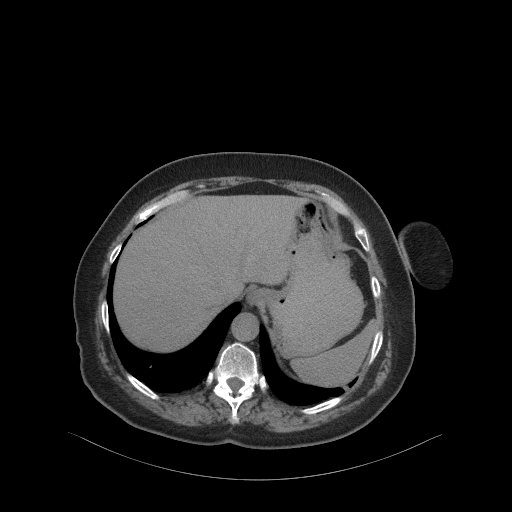

Generated VENOUS CT scan (A→B translation)

Full window (WL 1023.5, WW 4095 β†’ Low βˆ’1024, High +3071)

Original VENOUS CT scan

4Γ—3 grid: Rows show different image types (Original NATIVE, Reconstructed NATIVE, Original VENOUS, Generated VENOUS), Columns show windowing techniques (No Window, Lung Window, Mediastinum Window)